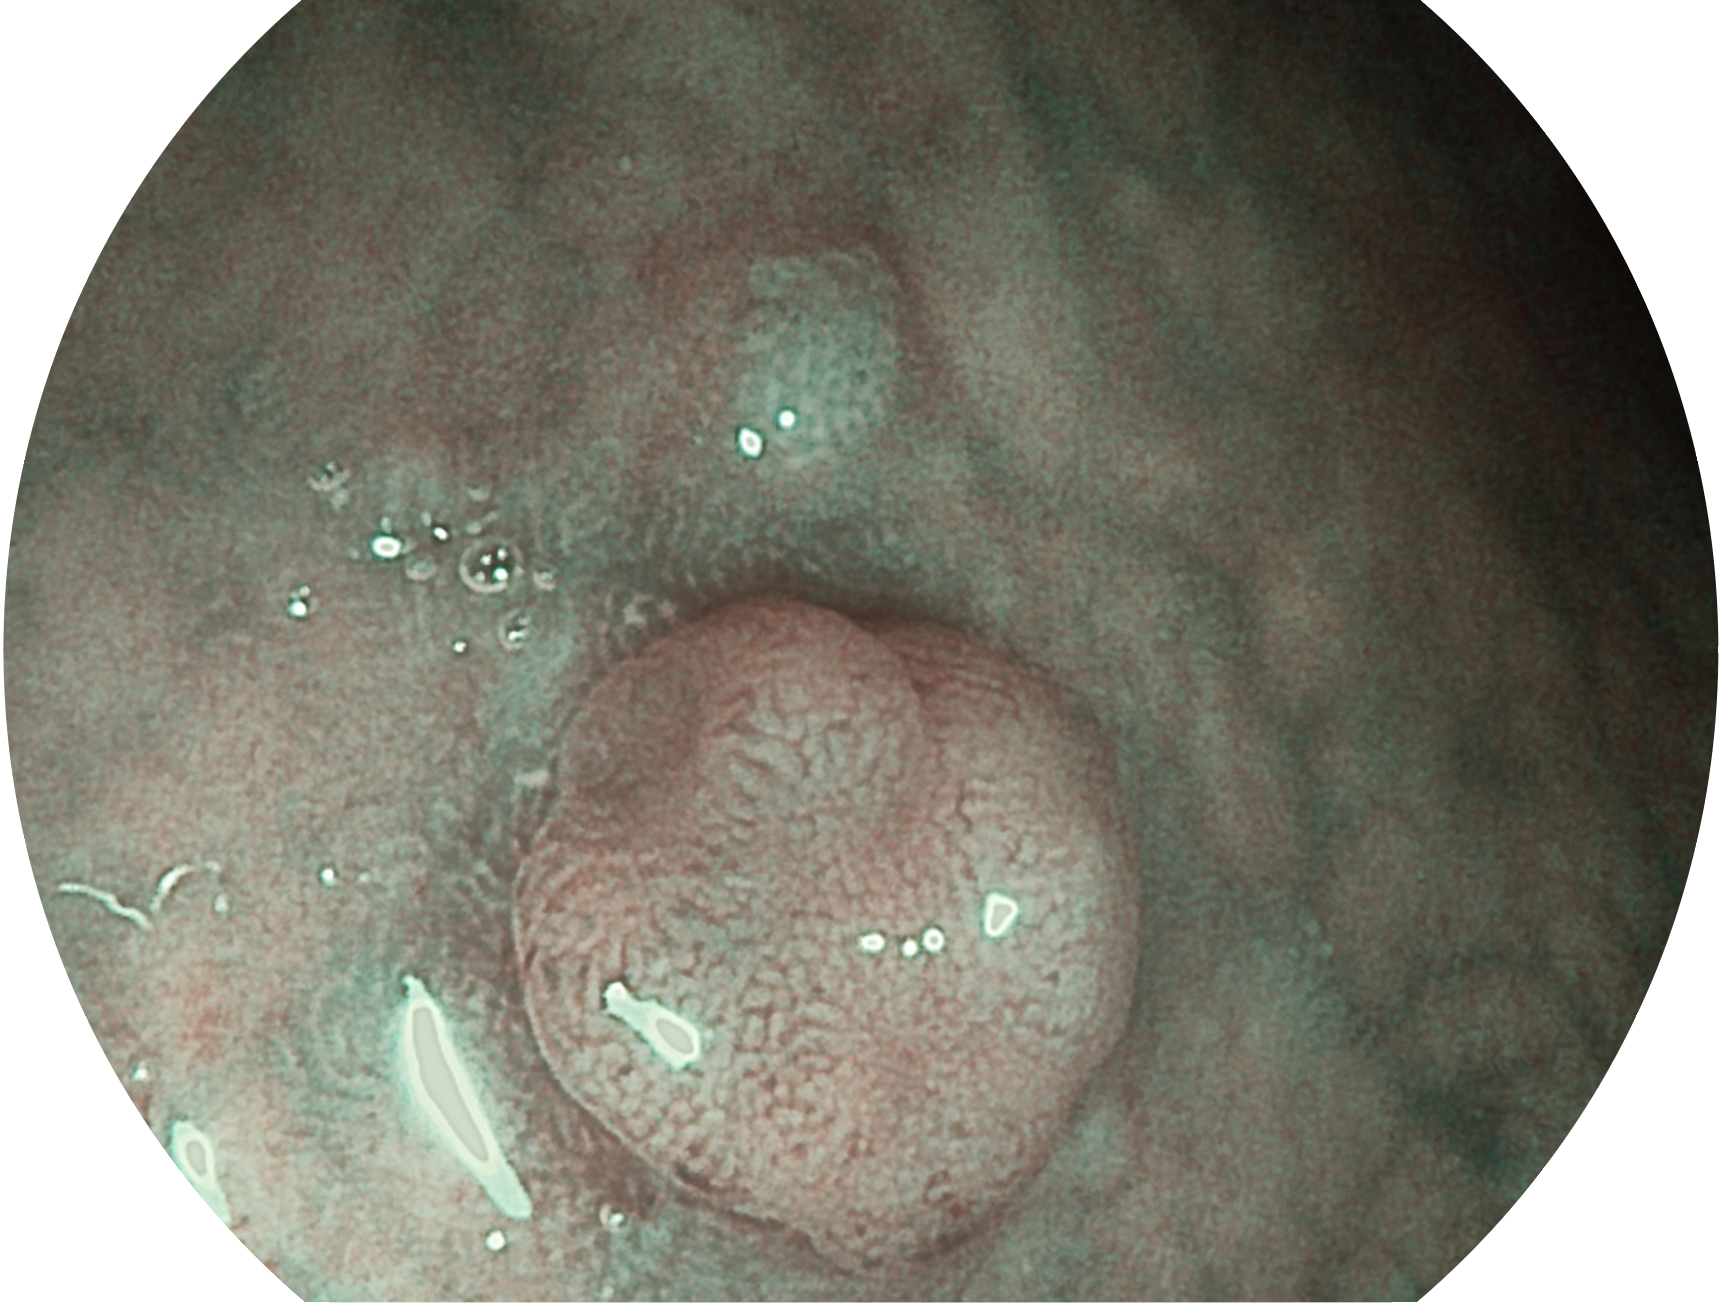

银河集团官网新开发的内镜染色技术,主要是基于多波长LED 光源的开发,VLS-55Q 四波长LED 光源是由四个不同颜色的LED光按照相应照明模式所规定的特定发光比例进行合束后形成,合束后形成的照明光的光谱由红光、绿光、蓝光及蓝紫光这四个不同的波段范围构成。具有更高光谱自由度,通过光谱比例的控制,实现了聚谱成像技术,英文全称为“Spectral Focused Imaging, SFI”,缩写为“SFI”和光电复合染色成像技术,英文全称为“Versatile Intelligent Staining Technology, VIST”,缩写为“VIST”。